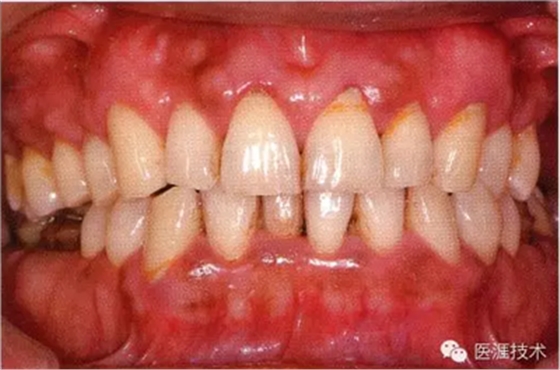

44歲牙周炎女性的臨床照片

44歲患有糖尿病病史(未治愈)。菌斑控制不良。通過(guò)牙周探診,全頜有4~8mm的牙周袋,在X光片中可以看到上頜前牙處中度牙槽骨吸收,磨牙處重度牙槽骨吸收。二次齲齒和根面齲齒也有發(fā)生。可以看到浮腫性腫脹,收到刺激后會(huì)出血。